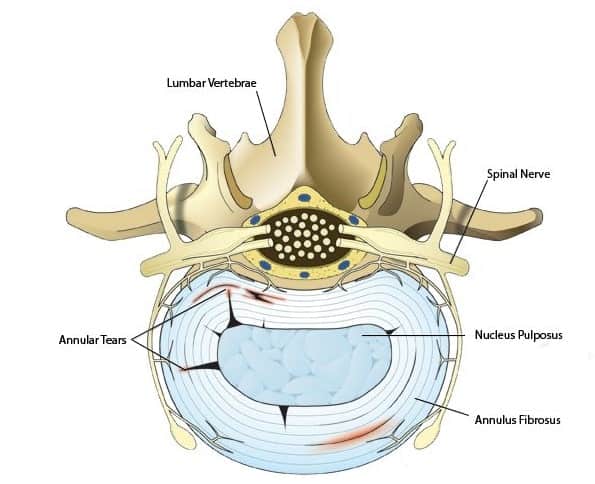

وظیفه اصلی ستون فقرات محافظت از طناب نخاعی، ریشههای عصبی و چندین اندام داخلی بدن و همچنین فراهم نمودن حمایت ساختاری و تعادل بدن به منظور حفظ وضعیت ایستاده و…